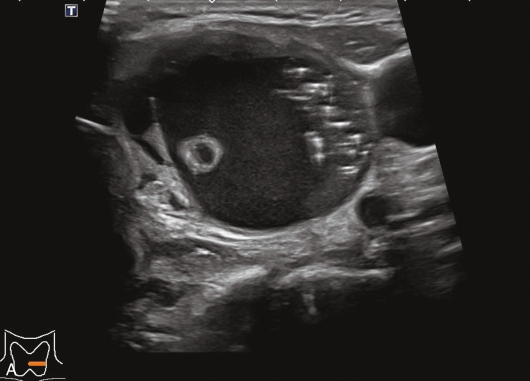

女性,51岁,因乏力就诊,无颈前区不适。

甲状腺囊肿常规超声表现为边界清晰、形态较规则的无回声结节,内可见点状强回声,后伴“彗星尾”征,CDFI内部无明显血流信号,见图1-3-1。

图1-3-1 甲状腺囊肿常规超声声像图

A.甲状腺左叶纵切面;B.CDFI血流图